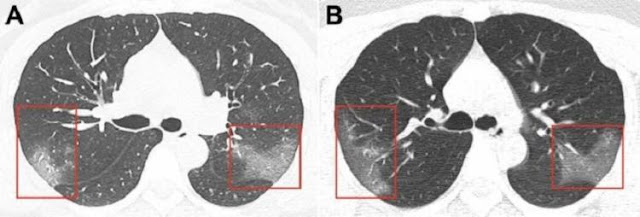

"Eles ofegam se andam um pouco mais rapidamente...Alguns pacientes podem ter uma queda de 20% a 30% na função pulmonar", pontuou Tsang. Ele também relatou que nove dos pacientes testados "apresentaram padrões semelhantes a 'vidro fosco' em todos eles, sugerindo que houve danos nos órgãos", disse.